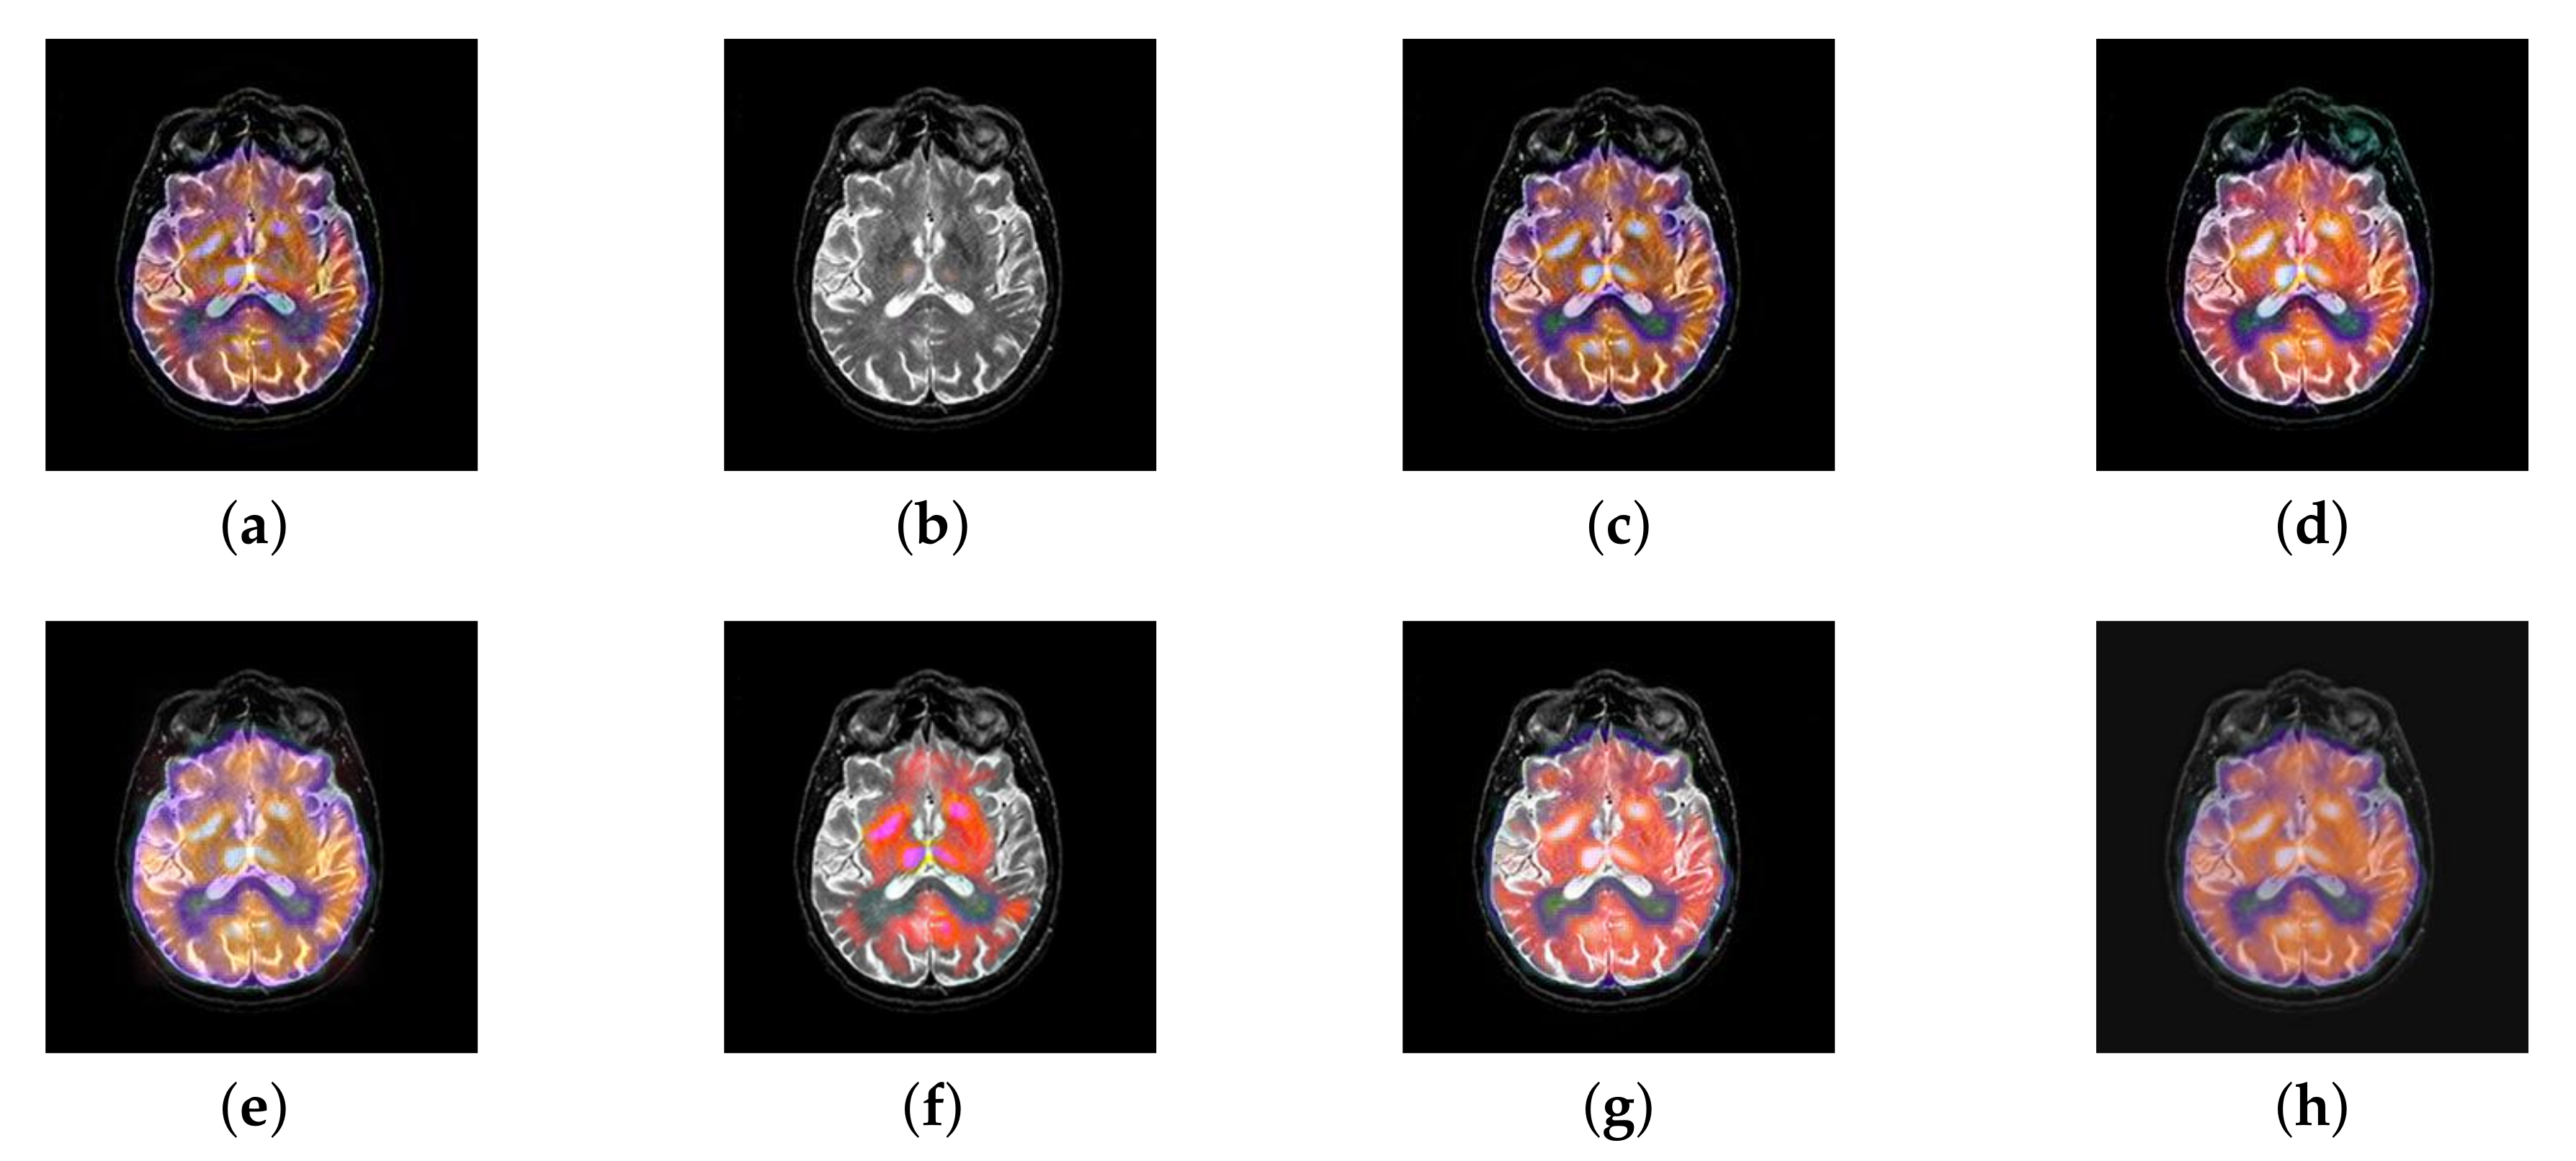

In this section, all FDG images are derived from the normal human brain, but the angle is chosen differently in Figure 24. In Figure 25, Figure 26, Figure 27 and Figure 28, we find that the color information obtained by the image fusion method based on NSCT, DTCWT, and LPSR is better preserved, but the structure information is lost more. The fusion image based on GFF, IGM, and FusionCNN method retains the complete structure information in the MRI image, but the color obtained from the FDG image is distorted. The image color information obtained by DDcGAN fusion method is too bright, resulting in unclear color area details and low contrast of color region. In contrast, the image obtained by our algorithm has moderate brightness of color information, complete structure information, and complete biological detail information.

Figure 25.

Fused medical images obtained by different algorithms (Figure 24a,b): (a) DTCWT, (b) GFF, (c) NSCT, (d) LPSR, (e) IGM, (f) FusionCNN, (g) DDcGAN, and (h) FusionNet.

Figure 26.

Fused medical images obtained by different algorithms (Figure 24c,d): (a) DTCWT, (b) GFF, (c) NSCT, (d) LPSR, (e) IGM, (f) FusionCNN, (g) DDcGAN, and (h) FusionNet.

Figure 27.

Fused medical images obtained by different algorithms (Figure 24e,f): (a) DTCWT, (b) GFF, (c) NSCT, (d) LPSR, (e) IGM, (f) FusionCNN, (g) DDcGAN, and (h) FusionNet.

Figure 28.

Fused medical images obtained by different algorithms (Figure 24g,h): (a) DTCWT, (b) GFF, (c) NSCT, (d) LPSR, (e) IGM, (f) FusionCNN, (g) DDcGAN, and (h) FusionNet.